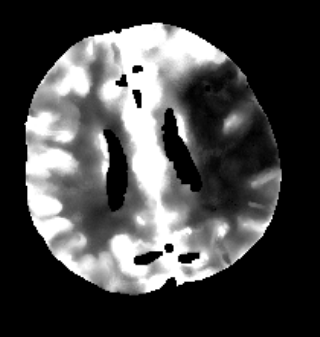

Furthermore mRay is capable of performing image processing tasks such as finding, visualizing and quantifying anomalies in tissue. In particular the image analysis module mRay VEOcore may be used to perform an automated processing of brain images from imaging modalities such as CT, CT-Perfusion, or MRI including a Diffusion Weighted Imaging (DWI) Module. As a result, changes in contrast over time are visualized as colored perfusion maps, including flow related parameters and tissue blood volume quantification.

The perfusion analysis of brain imaging data visualizes and quantifies tissue that is less supplied with blood (penumbra), oxygen deprived tissue caused by obstructed blood flow (core tissue) and the mismatch ratio between the two. The calculated values can be used to support decision making based on an assessment of the extent of tissue damage.

16.1. Overview

VEOcore is a fully automated image processing tool to calculate quantitative measures of affected brain tissue and healthy tissue. Therefore, this manual covers the instructions on how to interpret the results. It’s an extension the mRay Server application and the results can be viewed inside the mRay Client. Furthermore processed results can be automatically forwarded to the PACS.